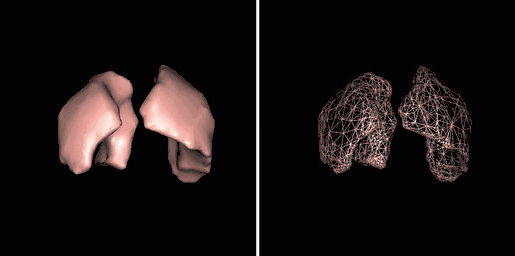

Surface Rendering

Surface rendering is also referred to as Shaded Surface Display (SSD) and involves generating surfaces from regions with similar voxel values in the 3D data as illustrated by the SPECT lung-perfusion scan shown in the left panel below:

The process involves the display of surfaces which might potentially exist within the 3D voxel data on the basis that the edges of objects can be expected to have similar voxel values. One approach is to use a grey-level thresholding technique where voxels are extracted once a threshold value is encountered in the line of the projection – see the following diagram. Triangles are then used to tesselate the extracted voxels, as shown in the right panel of the figure above – and the triangles are filled using a constant value with shading applied on the basis of simulating the effects of a fixed virtual light source – as shown in the left panel above.